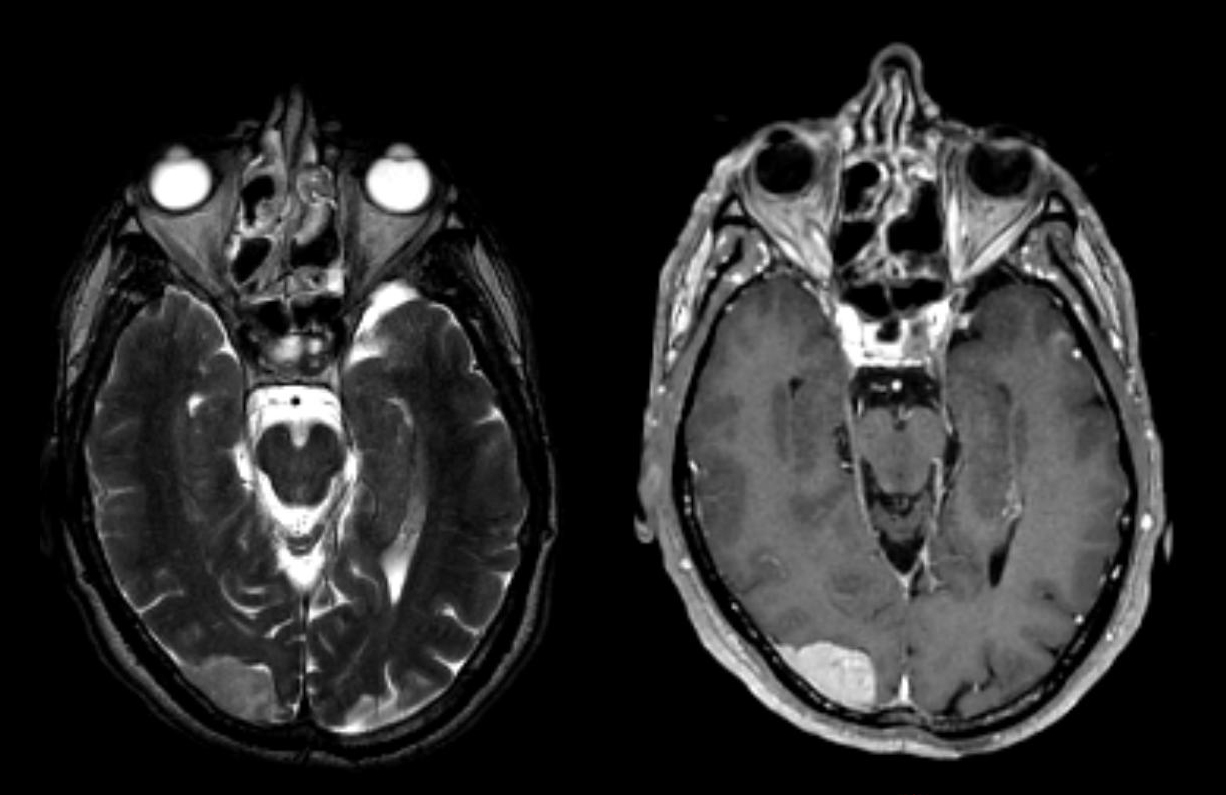

Une image vous interpelle sur l’IRM cérébrale :

À propos de l’imagerie cérébrale : il s’agit d’une image typique de méningiome : tumeur extraparenchymateuse, bien limitée, à base méningée, avec des prolongements méningés (ou queues le long des méninges) se rehaussant fortement et de façon homogène lors de l’injection de gadolinium. Il s’agît d’une tumeur bénigne et asymptomatique, elle ne nécessite donc aucune exploration ni aucun traitement.

De façon générale en radiologie tumorale, l’examen radiologique peut être suffisant à conclure à la bénignité d’une lésion. A contrario, la suspicion d’une lésion maligne impose la réalisation d’une biopsie. Les traitements antinéoplasiques sont des traitements à marge thérapeutique étroite, et ont une indication précise. La preuve histologique est indispensable à leur prescription d’autant plus que les stratégies thérapeutiques sont définies en fonction de critères histologiques (type histologique, grade tumoral) et des données de biologie moléculaire. Enfin, une lésion tumorale a potentiellement des diagnostics différentiels infectieux ou immunologiques.

À propos de la thérapeutique à envisager :

au niveau neurologique il n’y a pas de symptôme d’HTIC ni de signe d’engagement : cette lésion ne nécessite aucun traitement ;

au niveau oncologique : le patient a une maladie non métastatique, la chimiothérapie n’est pas le traitement de première intention.